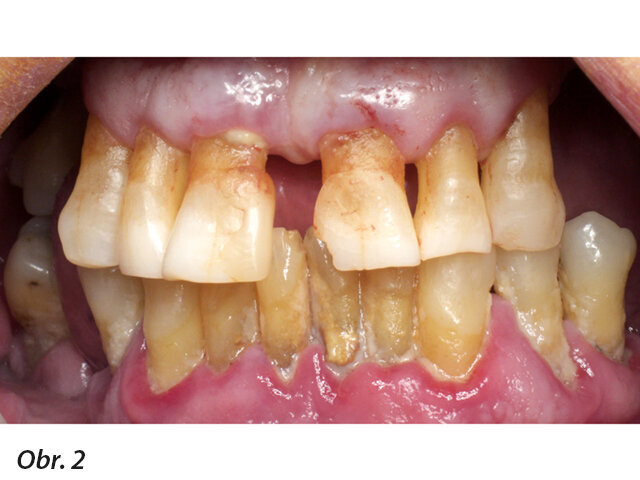

Iniciální situace

68letý pacient, bez lékařsky relevantní anamnézy a se zoufalým stavem chrupu, k nám byl delegován svým parodontologem. Byly pořízeny panoramatické CT snímky, na základě kterých jsme vyhodnotili dostupnost, dispozice a hustotu kostí (obr. 1 a 2). Po projednání různých možností léčby a s ohledem na celkovou klinickou, sociální a finanční situaci pacienta byla implantologická léčba s fixní dlouhodobě provizorní náhradou ve stejný den první volbou jak pro stomatologický tým, tak pro pacienta.

Cílem bylo okamžitě zatížit implantáty šroubovanou provizorní náhradou. Aby toho bylo dosaženo, byly naplánovány strategické extrakce při dočasném zachování některých zubů jako klíčových prvků, které při intraorálním skenování determinují pacientovu estetiku, výšku skusu a protetický oblouk. Rozhodli jsme se provést minimálně invazivní chirurgii s technikou flapless tam, kde to je možné, aby se zabránilo tomu, že by mobilizované tkáně mohly ovlivnit intraorální skenování. Pro rekonstrukci bylo naplánováno zavedení šesti implantátů Straumann Bone Level Tapered, Roxolid, SLActive se šroubovanými abutmenty (SRA).